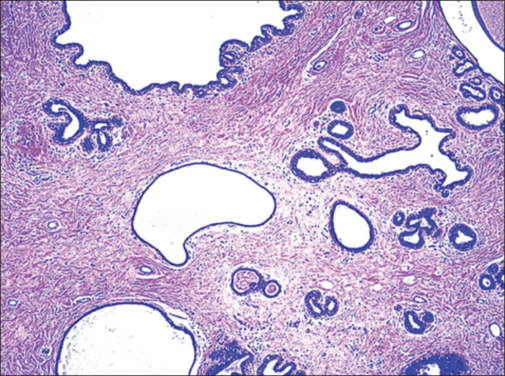

Hamartoma of the breast is a rare benign lesion that leads to unilateral breast enlargement with evidence of a localized palpable mass. Ultrasonography findings are typical and include a well-defined mass lesion of heterogeneous echotexture consisting of mixed echogenic and sonolucent areas. This case report describes a hamartoma of the breast in a 17-year-old female.

乳房错构瘤是一种罕见的良性病变,可导致单侧乳房增大,伴有局部可触及的肿块。超声检查结果是典型的,包括一个明确的肿块,回声质地不均匀,由混合的回声和透光区域组成。本病例报告描述了一名17岁女性的乳房错构瘤。